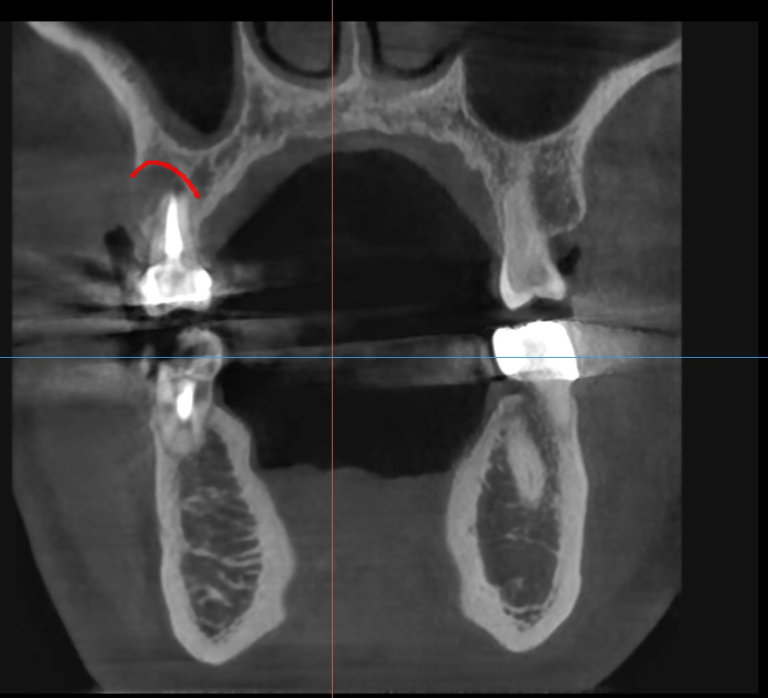

ct 상에서도 뼈가 너무 많이 녹아

발치를 추천드렸습니다.

더 냅둬야 붓는 것도 반복

잇몸 뼈는 계속 녹을테니까요.